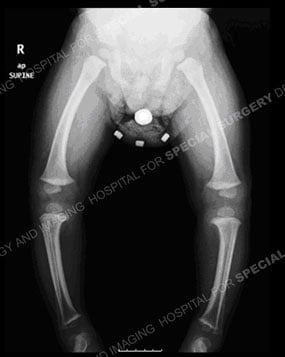

Photo and standing-alignment X-ray of a child with bowlegs.

Typically, a doctor will get the patient history, do a physical examination, and order a standing-alignment X-ray or EOS imaging of the leg bones from the hip to the ankle. Imaging helps the orthopedist determine the deformity’s location, magnitude and mechanical axis (where the bend occurs).